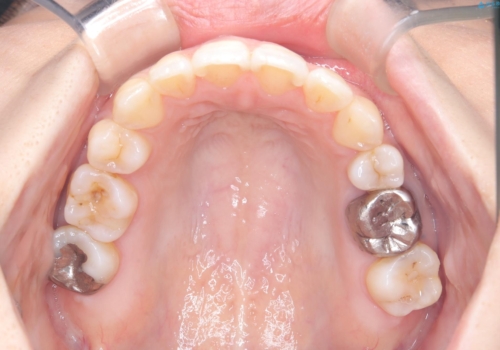

- 主訴:口元を下げて前突感を無くしたい、下の歯の凹凸も無くしたい

右側第二小臼歯、左側第一小臼歯、下顎両側第一大臼歯を抜歯しワイヤ-矯正を行いました。

骨格的顎の変位を認めたため、顔貌に対しピッタリ上下の歯の正中を合わせることは難しいと説明し、上下左右計4本小臼歯を抜歯しワイヤー矯正治療を行いました。